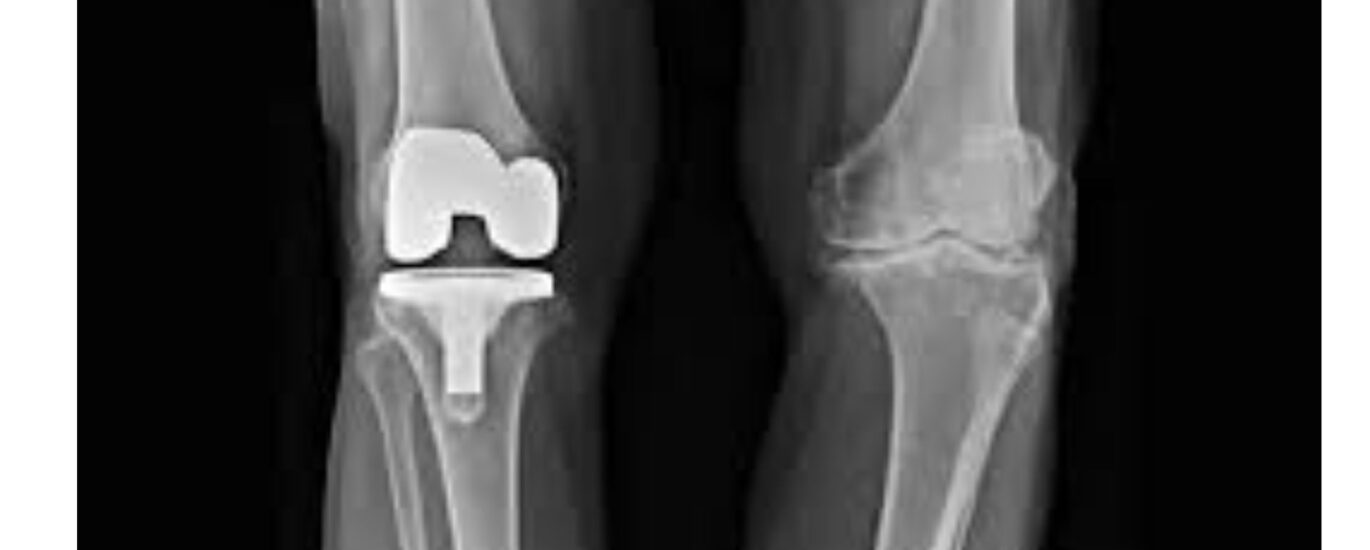

Knee replacement surgery is an effective and advanced treatment option which alleviates the symptoms associated with chronic knee pain, arthritis, and other knee conditions. This is recommended when non-surgical techniques are unable to provide any relief from the condition. During this surgery, the damaged portions of the knee joint are removed and replaced with an artificial prosthesis, which is made up of plastic, metal, or ceramic components.

Knee replacement surgery is a minimally invasive procedure which is done under either general or local anaesthesia. The surgeon makes small incisions near the knee joint and then carefully removes worn-out or damaged portions. After this, they replace it with prostheses, which are basically artificial implants made out of metal, plastic, or ceramic components. Once the implants are placed, doctors close the incision with the help of bandages for recovery.